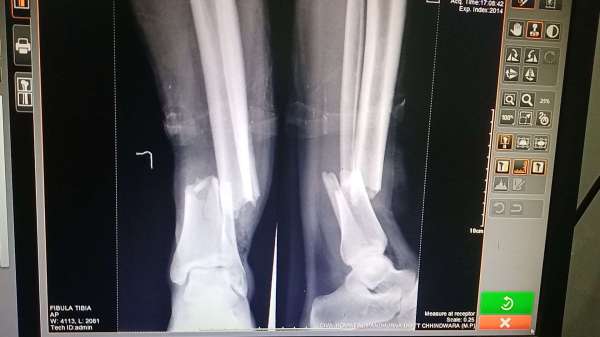

250 से अधिक हुए घायल, तीन गंभीरपत्थरबाजी में 250 से अधिक खिलाड़ी घायल हुए। देर शाम प्रशासन ने 145 लोगों के घायल होने की जानकारी दी। तीन लोग गंभीर रूप से घायल हुए। खारी वार्ड निवासी रामचंद्र खुरसंगे 75 साल का पैर फ्रेक्चर हो गया। इसी तरह सागर पिता शंकर कुमरे 21 साल का भी पैर फ्रेक्चर हो गया। संजय पिता सानु बड़ोदे 22 साल निवासी झिलपा को कंधे पर गंभीर चोंट आई उसे जिला अस्पताल रैफर किया गया।